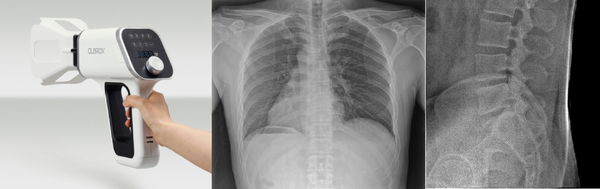

VSI의 주요제품인 ‘VX-100’은 FDA와 CE 인증을 완료하고 판매 중인 인체용 핸드헬드 X-ray다. CNT X-ray Tube를 적용해 낮은 발열로 냉각계를 축소하고 고분자-세라믹 차폐·절연 일체형 고체 몰딩을 적용해 2.4kg 경량화를 달성했다. 투과형 설계를 최적화해 낮은 전력으로도 충분한 관통력을 확보해 골반·척추 등 체간부 고두께·고산란 부위 촬영이 가능하다.

성인 복부·골반·요추는 부위 두께와 산란선 증가로 높은 노출 조건이 필요한 대표적 난부위로, 이들 부위를 임상 품질로 촬영하면 상대적으로 얇거나 고대비인 사지·흉부는 통상 더 수월하다. 2.4kg 폼팩터에서 척추·골반 촬영 성능을 임상 이미지로 확인했으며, 완충 시 약 500회 촬영이 가능해 ODA 환경에서도 여유 있게 운용할 수 있다.

CNT 기반 인체용 핸드헬드 X-ray 중 의료 인증과 실제 판매까지 이룬 사례는 현재로선 매우 드물다. VX-30과 VX-100은 미국 FDA 510(k)와 CE 인증을 확보했으며, 중소벤처기업부 혁신제품으로 지정되어 기술력을 공신력 있게 인정받았다.

▲ VX-100(左)과 VX-100으로 촬영한 X-RAY 사진(中, 右)